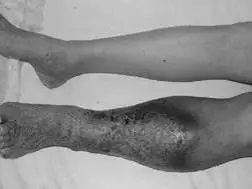

肺栓塞是静脉血栓最严重的临床表现,是人类死亡的第三大原因。肺栓塞可无症状,部分患者首发表现为猝死,其中突发致死性肺栓塞占34%,死前未能确诊的占59%,仅7%的早期死亡病例在死前确诊。深静脉血栓急性期会导致股青肿、股白肿,严重时截肢风险。深静脉血栓后综合征是一种慢性、进展性疾病,一般在深静脉血栓发病后6个月做出诊断。患者可表现为下肢血液循环障碍、静脉性跛行、皮肤难愈性溃疡甚至丧失劳动力 。

患肢突发肿胀、疼痛,活动后加重,抬高患肢后减轻,静脉血栓部位常有压痛,严重者出现股青肿、股白肿,均应进行静脉血栓检查;血栓脱落导致肺栓塞,突然发生不明原因的虚脱、面色苍白、出冷汗、呼吸困难者、胸痛、咳嗽等,严重者出现昏迷、猝死;慢性期出现下肢色素沉着、湿疹、静脉曲张,严重者出现足靴区的脂性硬皮病和溃疡 。